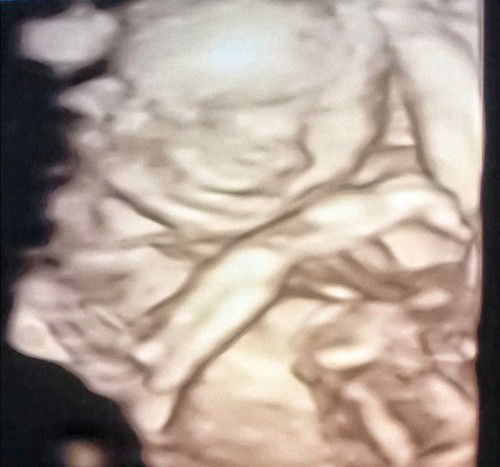

Hello, I had my miscarriage last march 2020 and now im 7 weeks pregnant, Hindi ko alam mga mommies if what is the best decision to do right now. Im currently working but naka bed rest ako for now. Iniisip ko kung itutuloy ko ba ang work or mag reresign nalang ako dahil nandito yung takot ko na baka makunan na naman ako. Thanks po. Godbless to us. #advicepls #pleasehelp #firstbaby